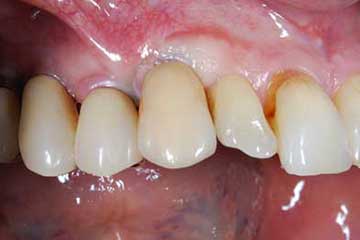

Con protesi fissa superiore e protesi fissa inferiore

sono stati sostituiti da 10 impianti, cioè protesi radicolari endo-ossee che sostengono le protesi fisse superiore ed inferiore.